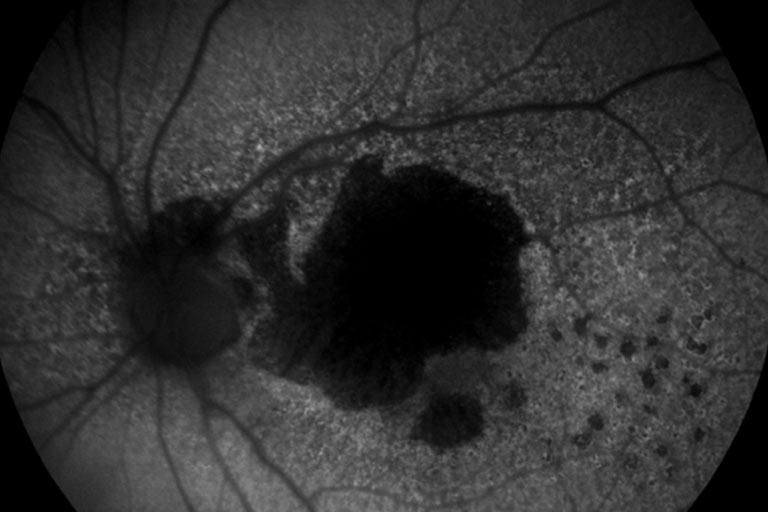

La Degeneración Macular Relacionada a la Edad (DMRE) es la primera causa de baja visión en el mundo desarrollado.